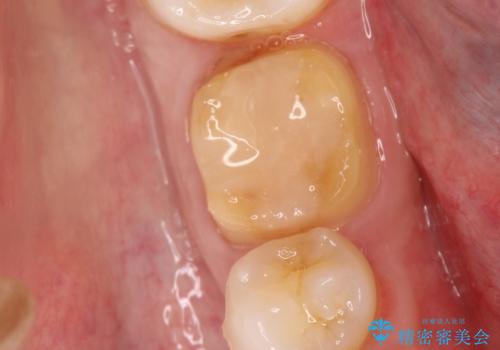

- 以前治療した右下の奥歯の歯の中が虫歯になっている気がするとのことで来院されました。

レントゲン上と視診上では確認できなかったのですが、患者様の希望もあり、一度かぶせ物を外して内部を確認し、オールセラミックを再度装着する計画としました。

やはり内部では少量の虫歯がありましたので、拡大鏡使用して虫歯を除去しました。